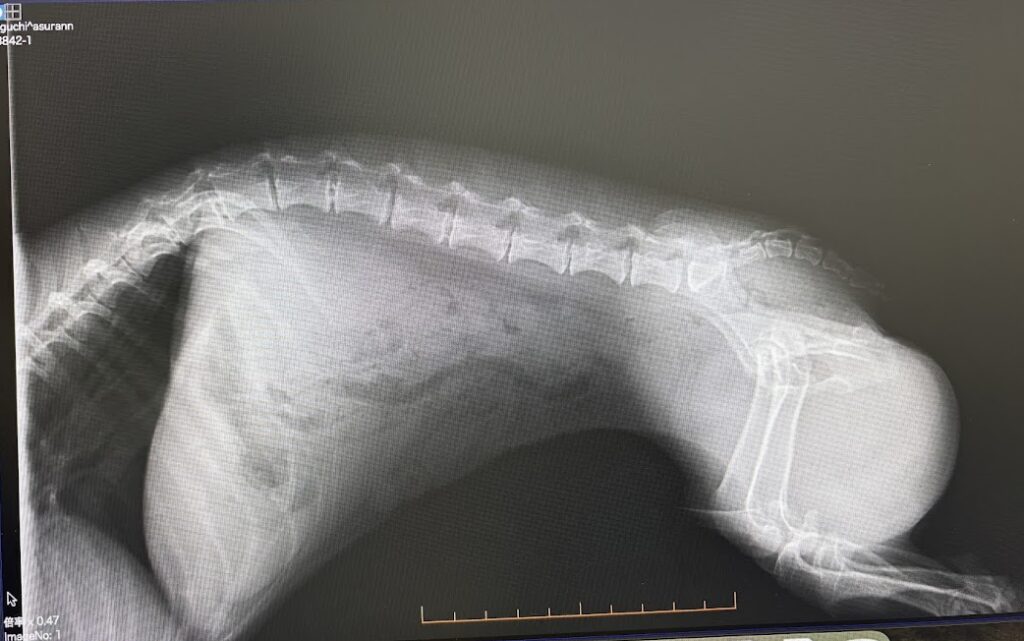

レントゲンの画像を見せてもらう

医者ではないので

見せてもらったが

説明を受けるも

わかったようなわからぬような。。。

ただ、この時点では

まだ自力歩行が可能で

動きが鈍いという状況下ぐらいで

骨と骨の端のところが石灰化して来てはいるけれど

それほど異常というわけでもなく

症状から考えると椎間板ヘルニアの

グレード2といったところですね